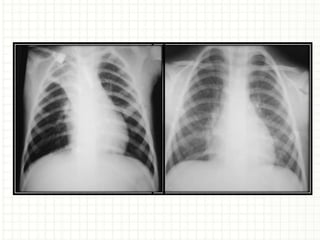

 Radiografia de tórax

Testes diagnósticos  Radiografiade tórax  Teste terapêutico  Espirometria com prova BD  Testes para atopia: cutâneos, IgE total e específica.